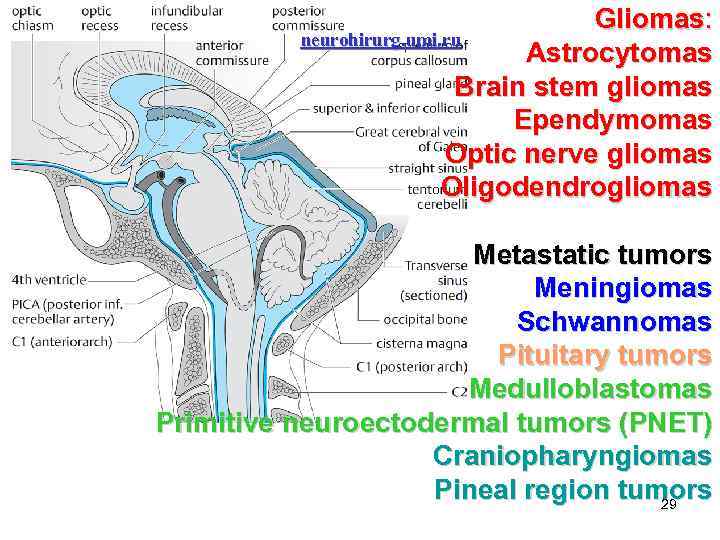

Gliomas: neurohirurg. umi. ru Astrocytomas Brain stem gliomas Ependymomas Optic nerve gliomas Oligodendrogliomas Metastatic tumors Meningiomas Schwannomas Pituitary tumors Medulloblastomas Primitive neuroectodermal tumors (PNET) Craniopharyngiomas Pineal region tumors 29